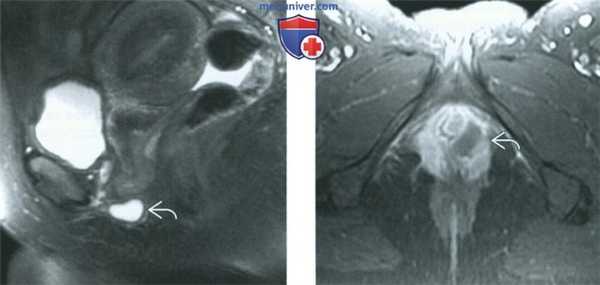

(Слева) При МРТ на Т2-ВИ в аксиальной плоскости у наружного отверстия уретры в переднем отделе входа во влагалище выявляется гипоинтенсивное объемное образование.

(Справа) При МРТ на Т1-ВИ FS в аксиальной плоскости у той же пациентки образование дает гиперинтенсивный сигнал. Локализация и МР-особенности объемного образования позволяют сделать заключение, что оно, скорее всего, является кистой железы Скина, осложнившейся кровоизлиянием.